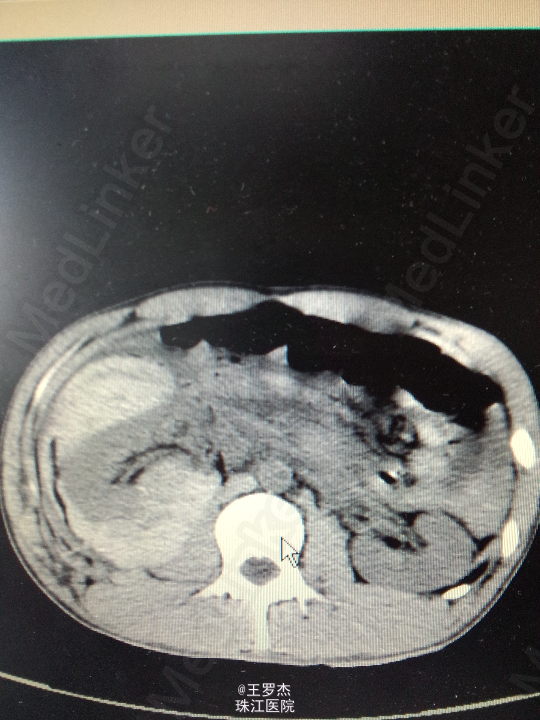

体格检查:体温:37℃,呼吸23次/分,脉率:84次/分,血压132/88mmHg。神情,查体配合。右季肋区可见3x4cm皮肤挫伤,腹部平软,双肾区无隆起,双侧输尿管走向无压痛,未触及包块,耻骨上区无充盈。 实验室检查:RBC 4.1,Hb 110g/L,WBC12.97,Cr187.0umol/L 辅助检查:CT右肾挫裂伤,包膜下大量积血,肾周、腹腔及盆腔内较多积液伴积血。

诊断治疗:右肾挫裂伤,保守治疗。3天后复查Hb89g/L,RBC2.65;复查CT提示包膜下及盆腔积血较前增多。请介入科会诊,行右肾动脉选择性栓塞。 介入:右肾挫裂伤,并上极动脉破裂出血及远端多处动静脉瘘形成,成功行超选择性病变血管栓塞术。